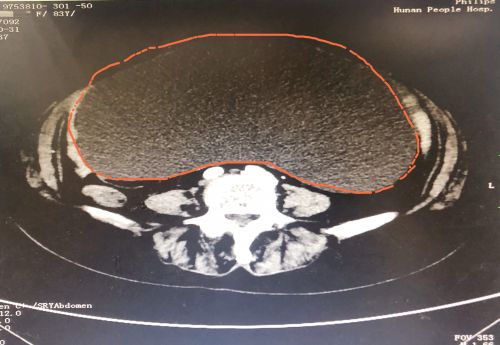

ct显示,肿瘤几乎占据老人整个盆腔和腹腔。

2021年1029日,彭娭毑住进捷克论坛 妇科病房。完善相关检查发现,巨大的肿瘤几乎占据她整个盆腔和腹腔,并且压迫肠道和膀胱,这也是老人尿频的原因。与此同时,术前血液检查发现了异常——全系细胞减少,进一步骨髓穿刺结果为:可疑B细胞淋巴瘤骨髓浸润。

经过充分讨论并做好充足的术前准备后,1112日,妇科黄薇主任团队在麻醉科、手术室的配合下,秉持无瘤操作原则,为老人施行单孔腹腔镜手术。在她肚脐上打一个小孔,缓慢引流出约4000毫升清亮的囊液。术中发现,左侧巨大的卵巢肿瘤与肠管致密大片粘连;精细分离后,顺利切除缩小的卵巢肿瘤和双侧附件,快速病检证实为“双侧卵巢浆液性囊腺瘤”。